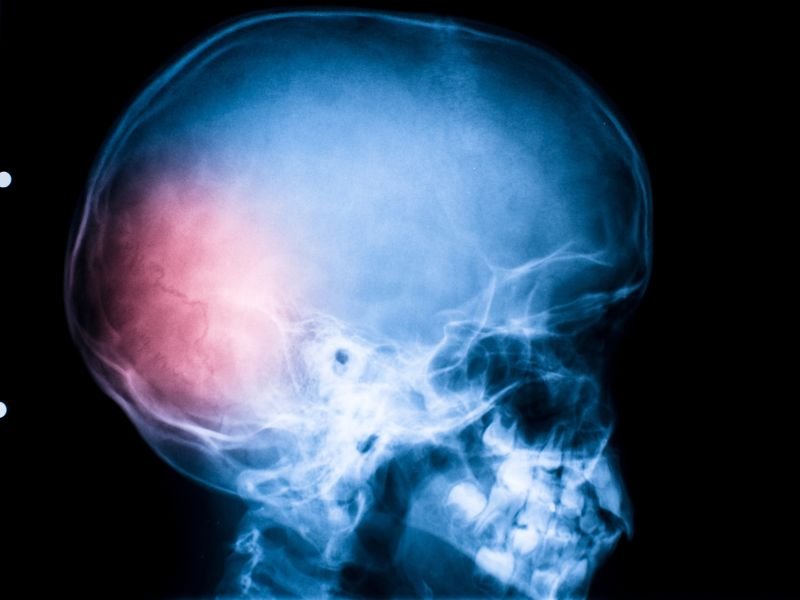

Tratamento Avançado para Enxaqueca em Tubarão A enxaqueca é uma condição neurológica que afeta milhões de pessoas em todo o mundo. Em Tubarão, o tratamento avançado para enxaqueca tem se tornado uma prioridade para muitos